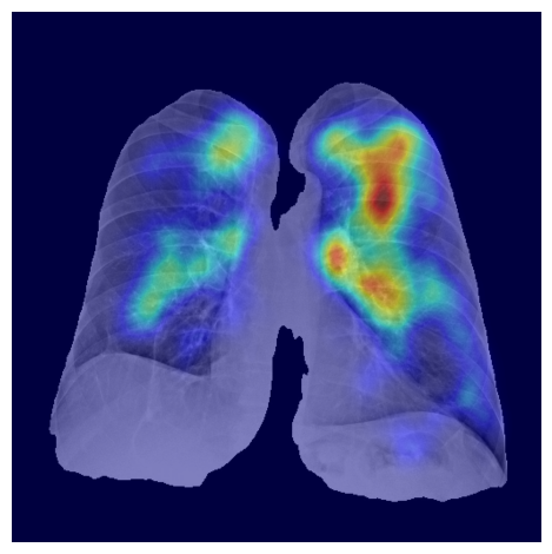

Results: The curriculum model achieved a mean AUC of .95 versus .89 for the baseline (p<.001, DeLong test), with improvements in sensitivity (70% vs 48%) and accuracy (82% vs 70%). Stratified analysis showed consistent gains across all difficulty bins (Easy to Very Hard), with significant p-values (p¡.01) for each. Grad-CAM visualizations confirmed more anatomically focused attention under curriculum learning.

Model Interpretability and Generalization

Refer to caption

(a) Healthy(1)

(b) NODE21

(c) Healthy(2)

(d) VinDr-CXR

Figure 5: Grad-CAM-based saliency maps illustrating model interpretability across datasets. Top row: Examples from NODE21 showing baseline (a) and curriculum-trained (b) models. Bottom row: Examples from VinDr-CXR demonstrating consistent attention patterns (c, d).

Grad-CAM visualizations showed that curriculum-trained models consistently focused on anatomically meaningful lung regions near nodules (Figure 5b), while baseline models activated broader, clinically irrelevant regions (Figure 5a). Similar attention patterns were observed across NODE21 and VinDr-CXR examples (Figure 5c,d), supporting interpretability and robustness.